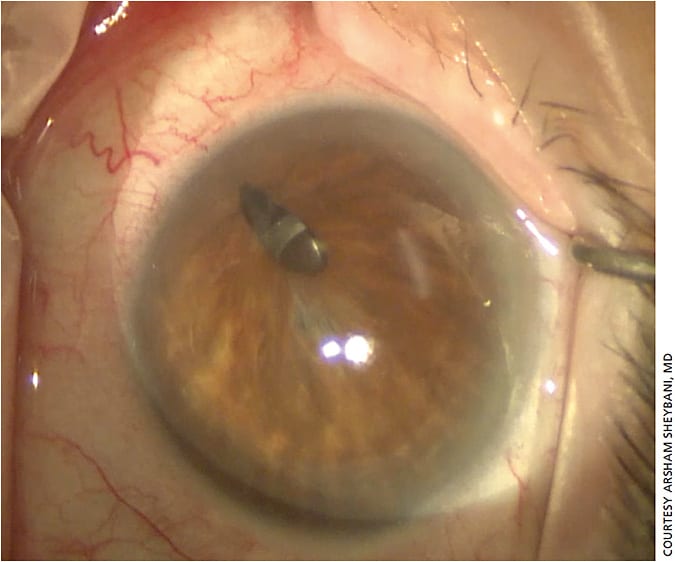

Asymptomatic patients are trickier, Dr. Sheybani notes. For example, in cases of corectopia, patients may end up with double vision because some light will go through the IOL while some may go around it only after cataract surgery is performed (Figure 4). But, suturing can sometimes cause more harm than good, he warns, especially if the iris is highly atrophic (Figure 5).

Phakic patients are “a lot more challenging” when there is a concurrent need for iris repair, says Arsham Sheybani, MD, of Washington University School of Medicine in St. Louis, Mo. Often the cause of iris damage is trauma (if the trauma was nonpenetrating, or never required surgery, the full iris tissue may be there). Several scenarios can lead to iris repair surgery, including:

“The issue then becomes, how much tissue is there? If the iris was operated on before and the patient lost tissue, it’s a very different discussion,” Dr. Sheybani says (Figure 3).